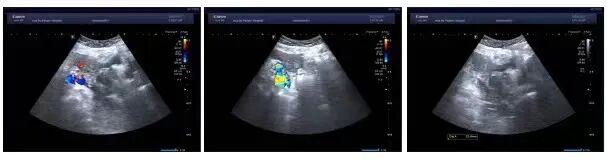

65岁的陈女士,因反复口干、多尿多饮、伴疲劳乏力,偶有胸闷,监测空腹指尖血糖超过11mmol/L,来我院内分泌科住院治疗,入院后完善相关检查,其中在子宫双附件彩超筛查中发现子宫上方见一类圆形低回声团,大小约37x32x37mm,边界不清,内部回声不均匀,这意味着不排除肿瘤可能。在积极控制血糖的同时,进一步完善了盆腔MR增强等针对性检查,结果提示:双侧附件区、

子宫双附件彩超